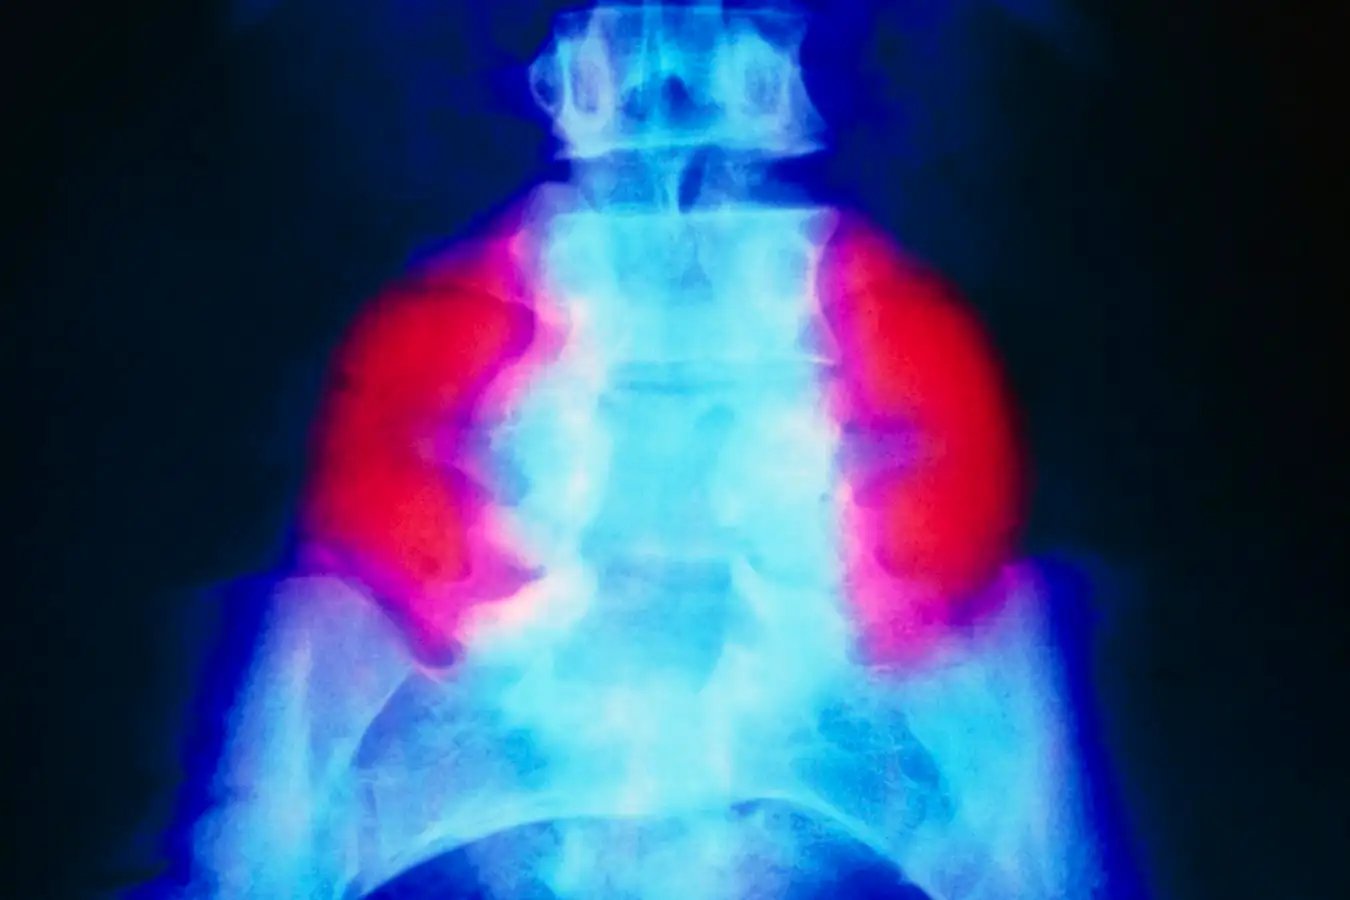

A false-colour X-ray exhibiting a big neural tube defect (crimson) on each side of the decrease again in somebody with spina bifida

SCIENCE PHOTO LIBRARY